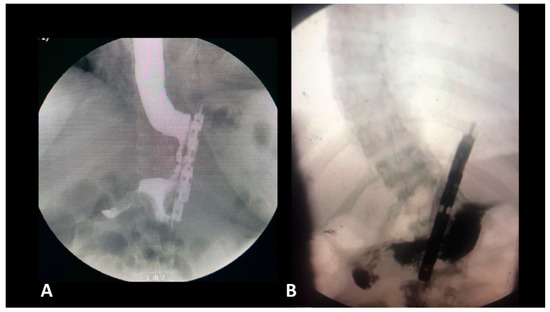

- The presence of a distal opening at the bottom of the BariClip makes the procedure a low-pressure system. It balances the pressures with the excluded part of the stomach, thus allowing for a possible acid or bile reflux to go towards the fundus, to the excluded portion of the stomach and not the esophagus, like in the illustrated upper GI swallow (Figure 2).